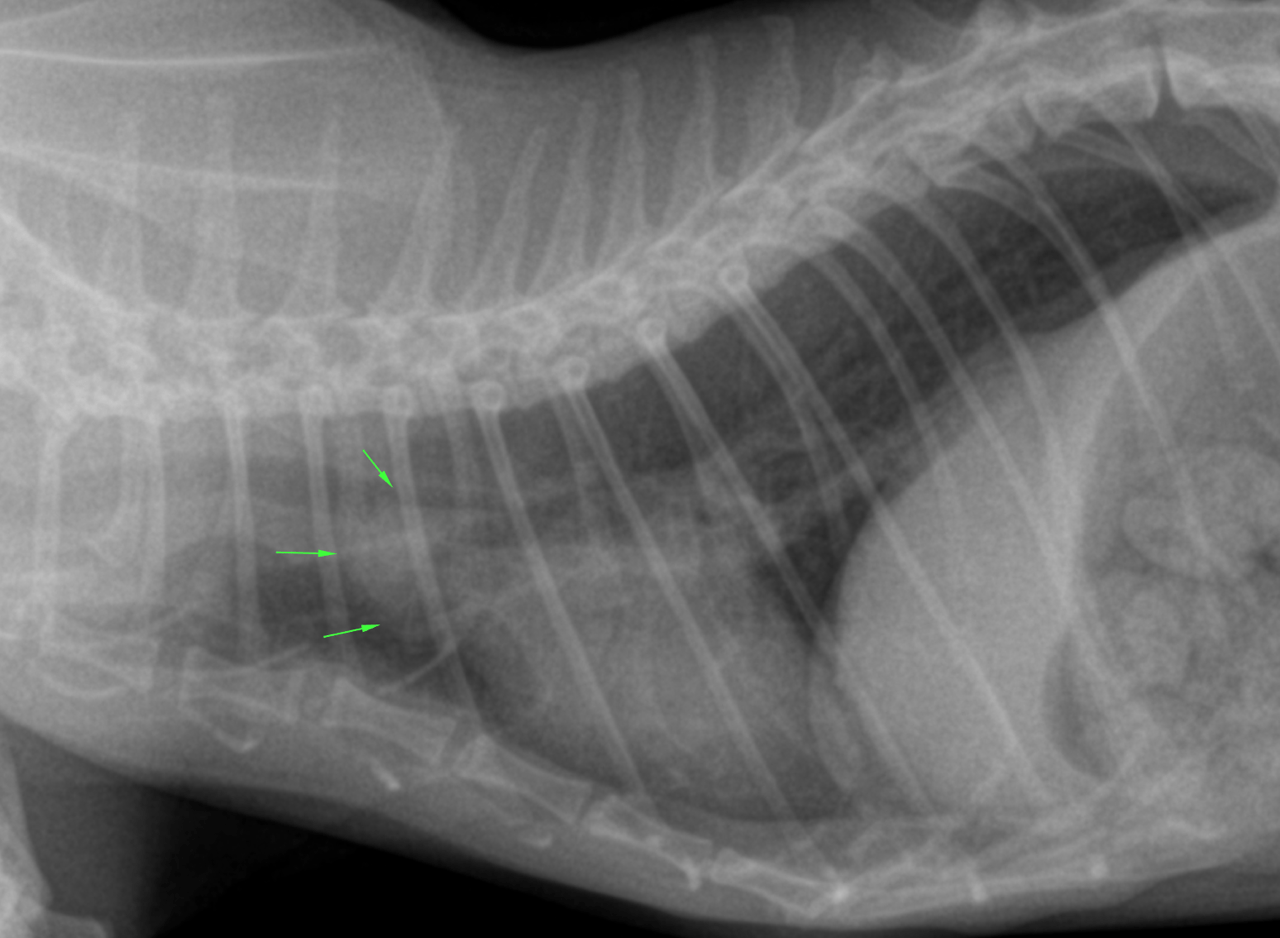

lateral and DV thorax, right lateral neck – The patient was thin.

Osseous structures:

Mild degenerative changes were associated with the axial skeleton.

Intrathoracic structures:

The esophagus was not seen. The course of the trachea was normal. The cardiac silhouette was within normal limits. There was a redundant aortic arch. The caudal vena cava and pulmonary vessels were thin. There was no mediastinal widening.

The chest was funnel shaped. The lung presented a mild generalized thinwalled bronchointerstitial pattern. There was no air trapping. There were no signs of expiratory obstruction. There were no signs of pneumonia, congestive heart failure, pulmonary edema or pleural effusion.

DX

The lung changes are most compatible with a normal age related bronchointerstitial pattern.